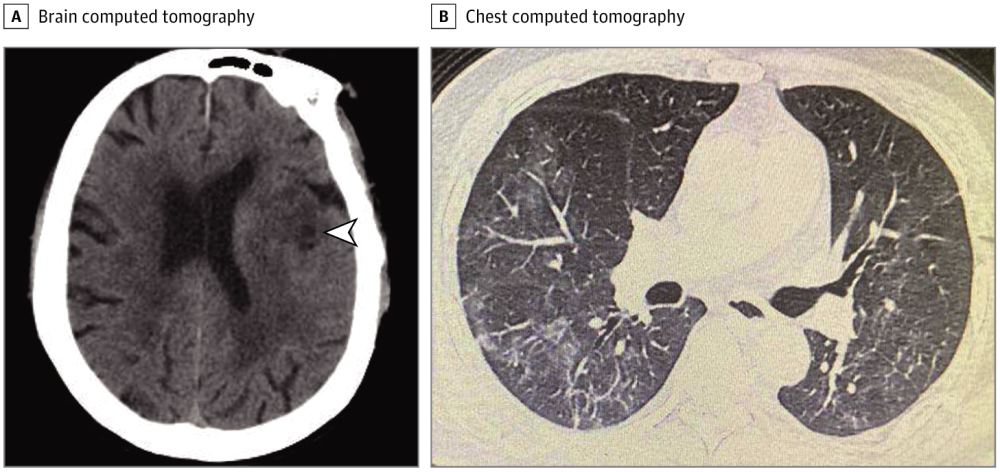

值得注意的是,除了出现脑血管疾病和意识障碍外,大部分神经系统症状还出现在发病早期(中位时间1-2天)。在这项研究中的6例出现急性脑血管病的患者,2例是因突发偏瘫来到急诊科就诊,当时并无COVID-19典型症状,如发热、咳嗽、厌食、腹泻。随后肺部CT显示他们肺部异常,后期核酸检测后被确诊为COVID-19。

也有部分一开始有发烧和头痛症状,在最初经血常规检测和肺部CT筛查排除COVID-19后被送到神经内科病房。然而,几天后,这部分患者出现了典型的COVID-19症状,如咳嗽、喉痛、淋巴细胞计数、肺CT毛玻璃样阴影。经核酸检测阳性后确诊为COVID-19,最终转到隔离病房。